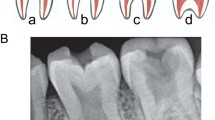

A Panoramic radiograph of the affected boy. There is dental crowding and delayed exfoliation of several primary teeth. Mesotaurodontism of the upper and lower first permanent molars is evident. The mandibular condyles lack a constriction at the neck. B High-arched palate. C Abnormal shape and decreased density of C2. D Mesotaurodontism of his first permanent molars.

The panoramic and cephalometric radiographs revealed retained primary mandibular incisors (72 and 82). There was a delay in the eruption and root apexification of the permanent teeth by approximately 3 years. The first permanent molars, especially the 36 and 46, showed features of mesotaurodontism (Fig. 3A, D). The lamina dura was absent and there was generalised rarefaction of the jaw with thinning of the cortical bone. The neck of the mandibular condyle lacked its normal constriction. A cephalometric analysis (Supplementary Fig. 1) indicated a steep cranial base, a skeletal Class III jaw relationship and a dental Class III molar relationship. The mandible and maxilla were retrognathic resulting in a flat facial profile. The sella turcica appeared small but was found to be within normal range; it had a narrow opening but no bridging (Supplementary Fig. 1). The maxillary sinuses appeared relatively opacified on the panoramic radiographic but were clearly visible on the lateral skull and the cephalometric radiographs.